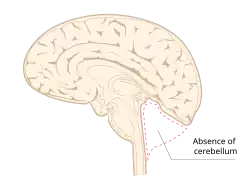

Cerebellar agenesis

Cerebellar agenesis is a rare condition in which a brain develops without the cerebellum. The cerebellum controls smooth movement, and when it does not develop, the rest of the brain must compensate, which it cannot do completely.[1] The condition is not fatal on its own, but people born without a cerebellum experience severe developmental delays, language deficits, and neurological abnormalities.[2] As children with cerebellar agenesis get older, their movements usually improve.[3] It can co-exist with other severe malformations of the central nervous system, like anencephaly, holoprosencephaly, and microencephaly.[1]

The condition was first reported in 1831. Ten cases had been reported as of 1998.[1] Agenesis of one half or another part of the cerebellum is more common than complete agenesis.[4]